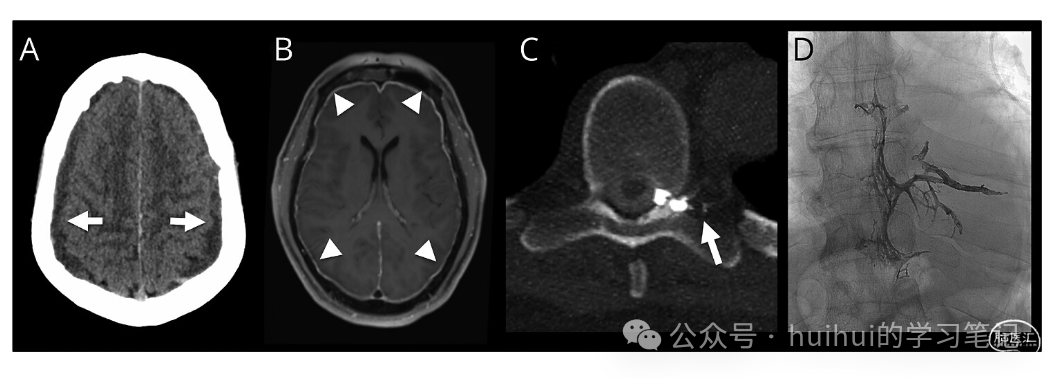

一名 65 岁男性出现 3 个月的每日直立性头痛和顽固性恶心,无外伤或出血素质。检查注意到右面部下垂波动,直立时唤醒减少,平躺时改善。头部 CT 显示双侧硬膜下积液,MRI 显示自发性颅内低血压 (SIH) 的柱头,包括脑下垂(图 1 和 2)。脊柱 MRI 显示小的神经周围憩室,无硬膜外液体。侧卧位动态 CT 脊髓造影1显示左侧 T8 CSF 静脉瘘(图 1C)。瘘管经静脉栓塞术(图 1D)导致第一天头痛、恶心和意识水平得到改善,位置神经功能缺损在 4 天内完全消退。48 小时重复脑部 MRI 显示脑下垂、静脉扩张和蛛网膜颗粒新出现明显改善(图 2)。治疗后数月通常可以看到 MRI SIH 结果的改善;然而,尚未很好地描述 48 小时内的快速改善。